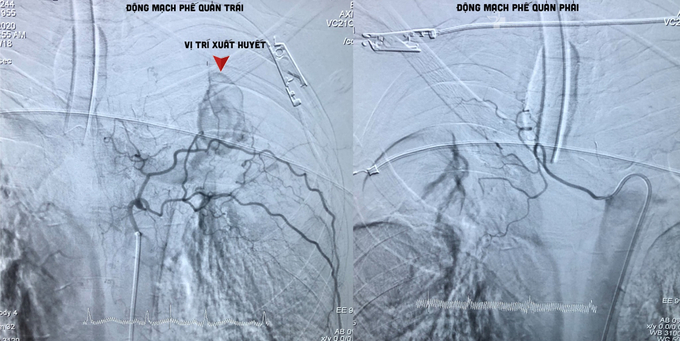

Sau khi xem xét, đánh giá tình hình, các bác sĩ quyết định can thiệp xử lý nội mạch, bằng kỹ thuật nút tắc động mạch phế quản cầm máu BAE (bronchial artery embolization) đối với bệnh nhân.

Dưới màn hình tăng sáng của máy chụp mạch số xóa nền (DSA), bác sĩ đặt một ống thông nhỏ đi từ động mạch đùi đến động mạch phế quản đang chảy máu. Sau đó, một ống thông có kích thước nhỏ hơn tiếp tục được luồn một cách chọn lọc vào trong lòng động mạch phế quản bị tổn thương để bơm chất nút mạch.

Sau can thiệp, các mạch máu động mạch phế quản gây tình trạng xuất huyết đã được nút lại kịp thời. Bệnh nhân qua cơn nguy kịch.